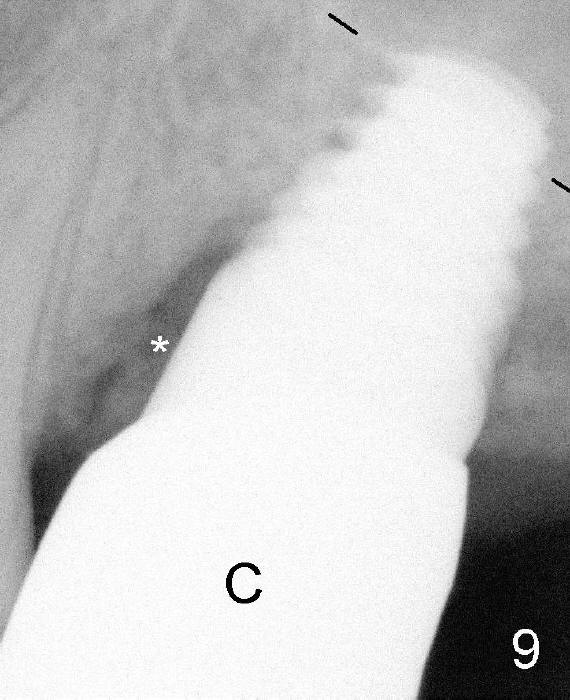

Fig.5 (immediately post implantation (I), 8x14 mm). *: remaining mesial socket

Fig.9 (5.5 months post implantation, immediately post cementation of the crown (C). The mesial socket has apparently decreased in size and increased in density.